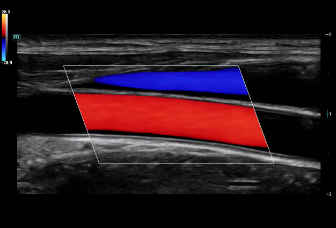

Consona presenta soluzioni nuove e concrete, che aiutano a effettuare diagnosi efficaci con semplicitĂ , rivolgendosi a un'ampia platea di pazienti. La serie mette a disposizione strumenti estremamente avanzati per rimanere all'avanguardia nella diagnosi cardiovascolare.

Galleria di immagini